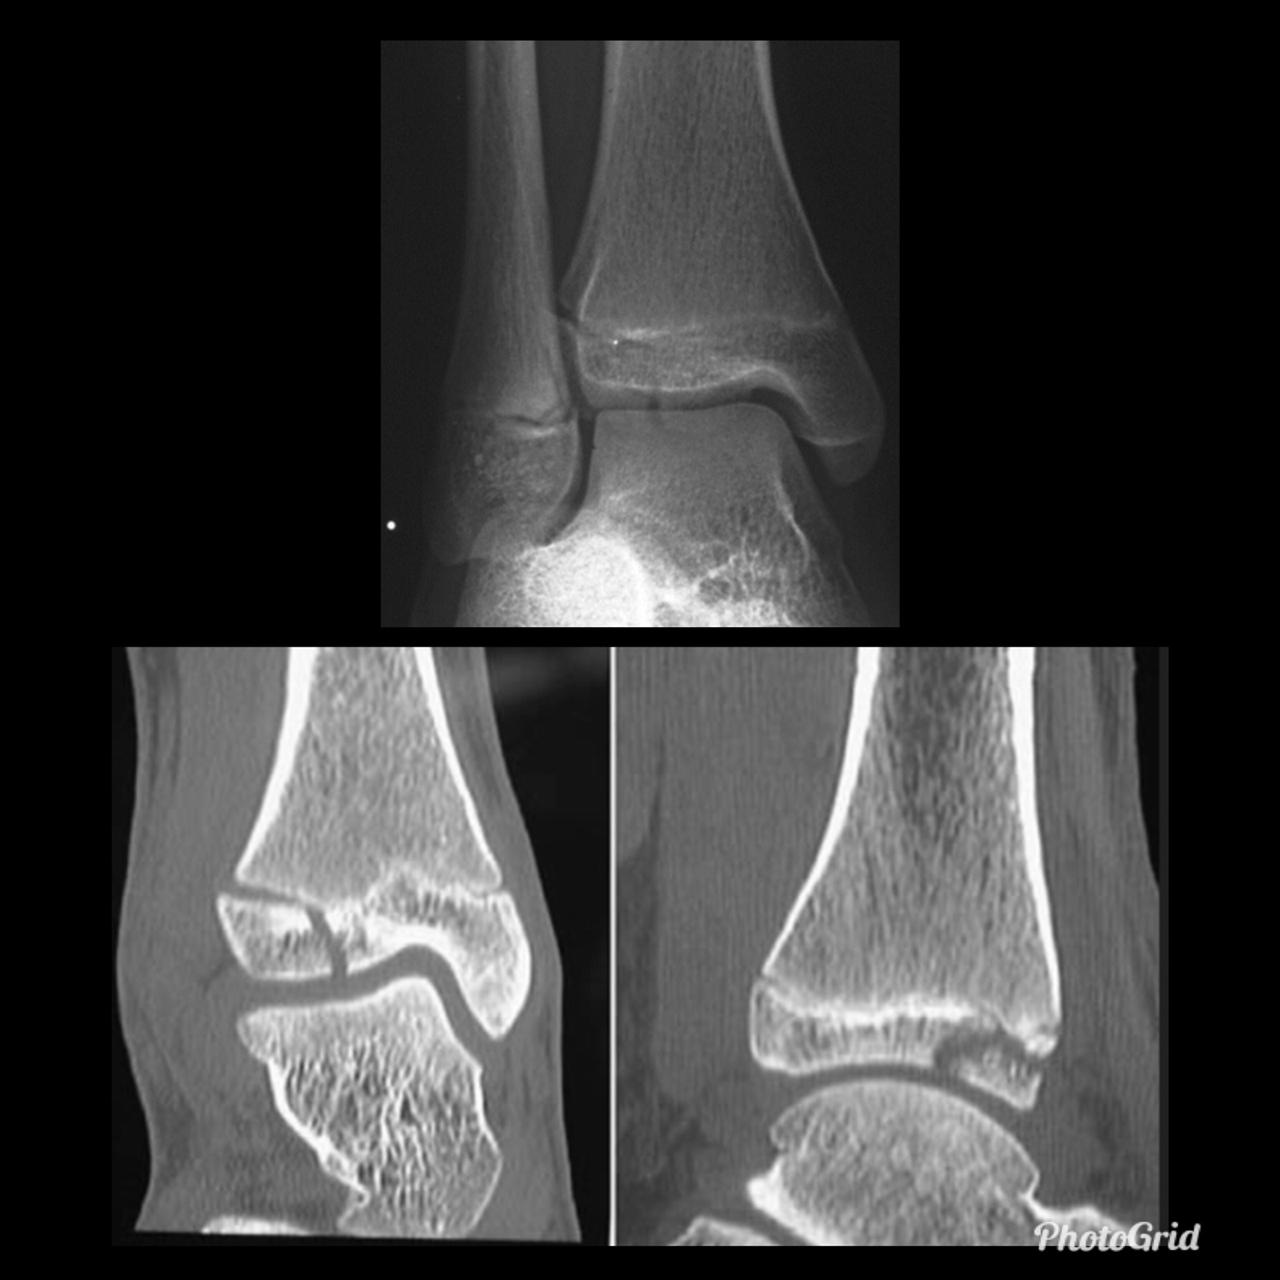

A Tillaux fracture is a traumatic Salter–Harris type III fracture through the anterolateral aspect of the distal tibial epiphysis, with variable amounts of displacement.

It accounts for 3-5% of pediatric ankle fractures and more commonly seen in girls. Tillaux feacture is seen in children nearing skeletal maturity (12-14 years old), when the medial epiphysis had closed but before the lateral side has done so.

The fracture commonly results from an abduction-external rotation force, causing the anterior tibiofibular ligament to avulse the anterolateral corner of the distal tibial epiphysis, at the opposite end to a Wagstaffe-Le Fort avulsion fracture, resulting in a Salter Harris Type III fracture.

Variability in fracture pattern is due to progression of physeal closure as anterolateral part of distal tibial physis is the last to close. When the lateral physis is the only portion not fused, external rotation may lead to Tillaux or Triplane fractures. Lack of coronal plane fracture in the posterior distal tibial metaphysis distinguishes this fracture from a triplane fracture.

Associated conditions commonly seen with this fracture are distal fibular fracture (usually SH I or II) and ipsilateral tibial shaft fracture.

If the displacement at fracture is less than 2 mm, it may be managed conservatively. However, displacement requires open reduction and internal fixation, especially when displacement is over 2 mm.

As with any intra-articular fracture if a step is left in the articular surface, then the joint will go on to premature secondary osteoarthritis.